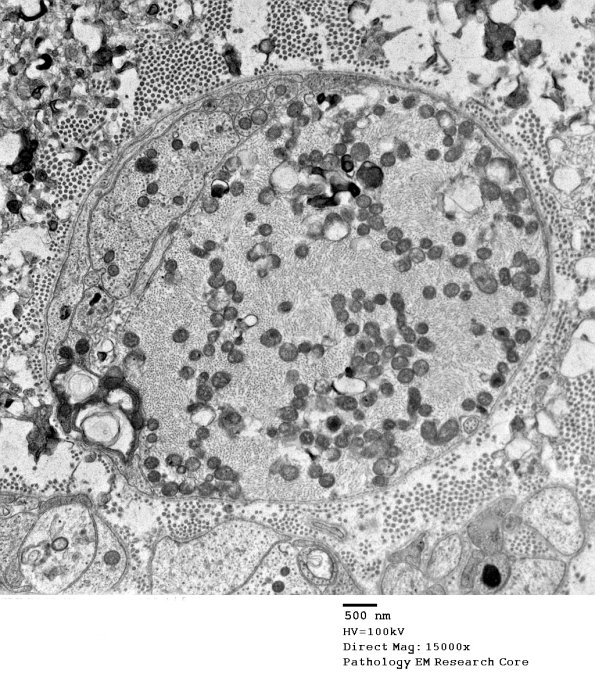

Only occasional axons are swollen with mitochondria and neurofilaments. (electron micrograph)